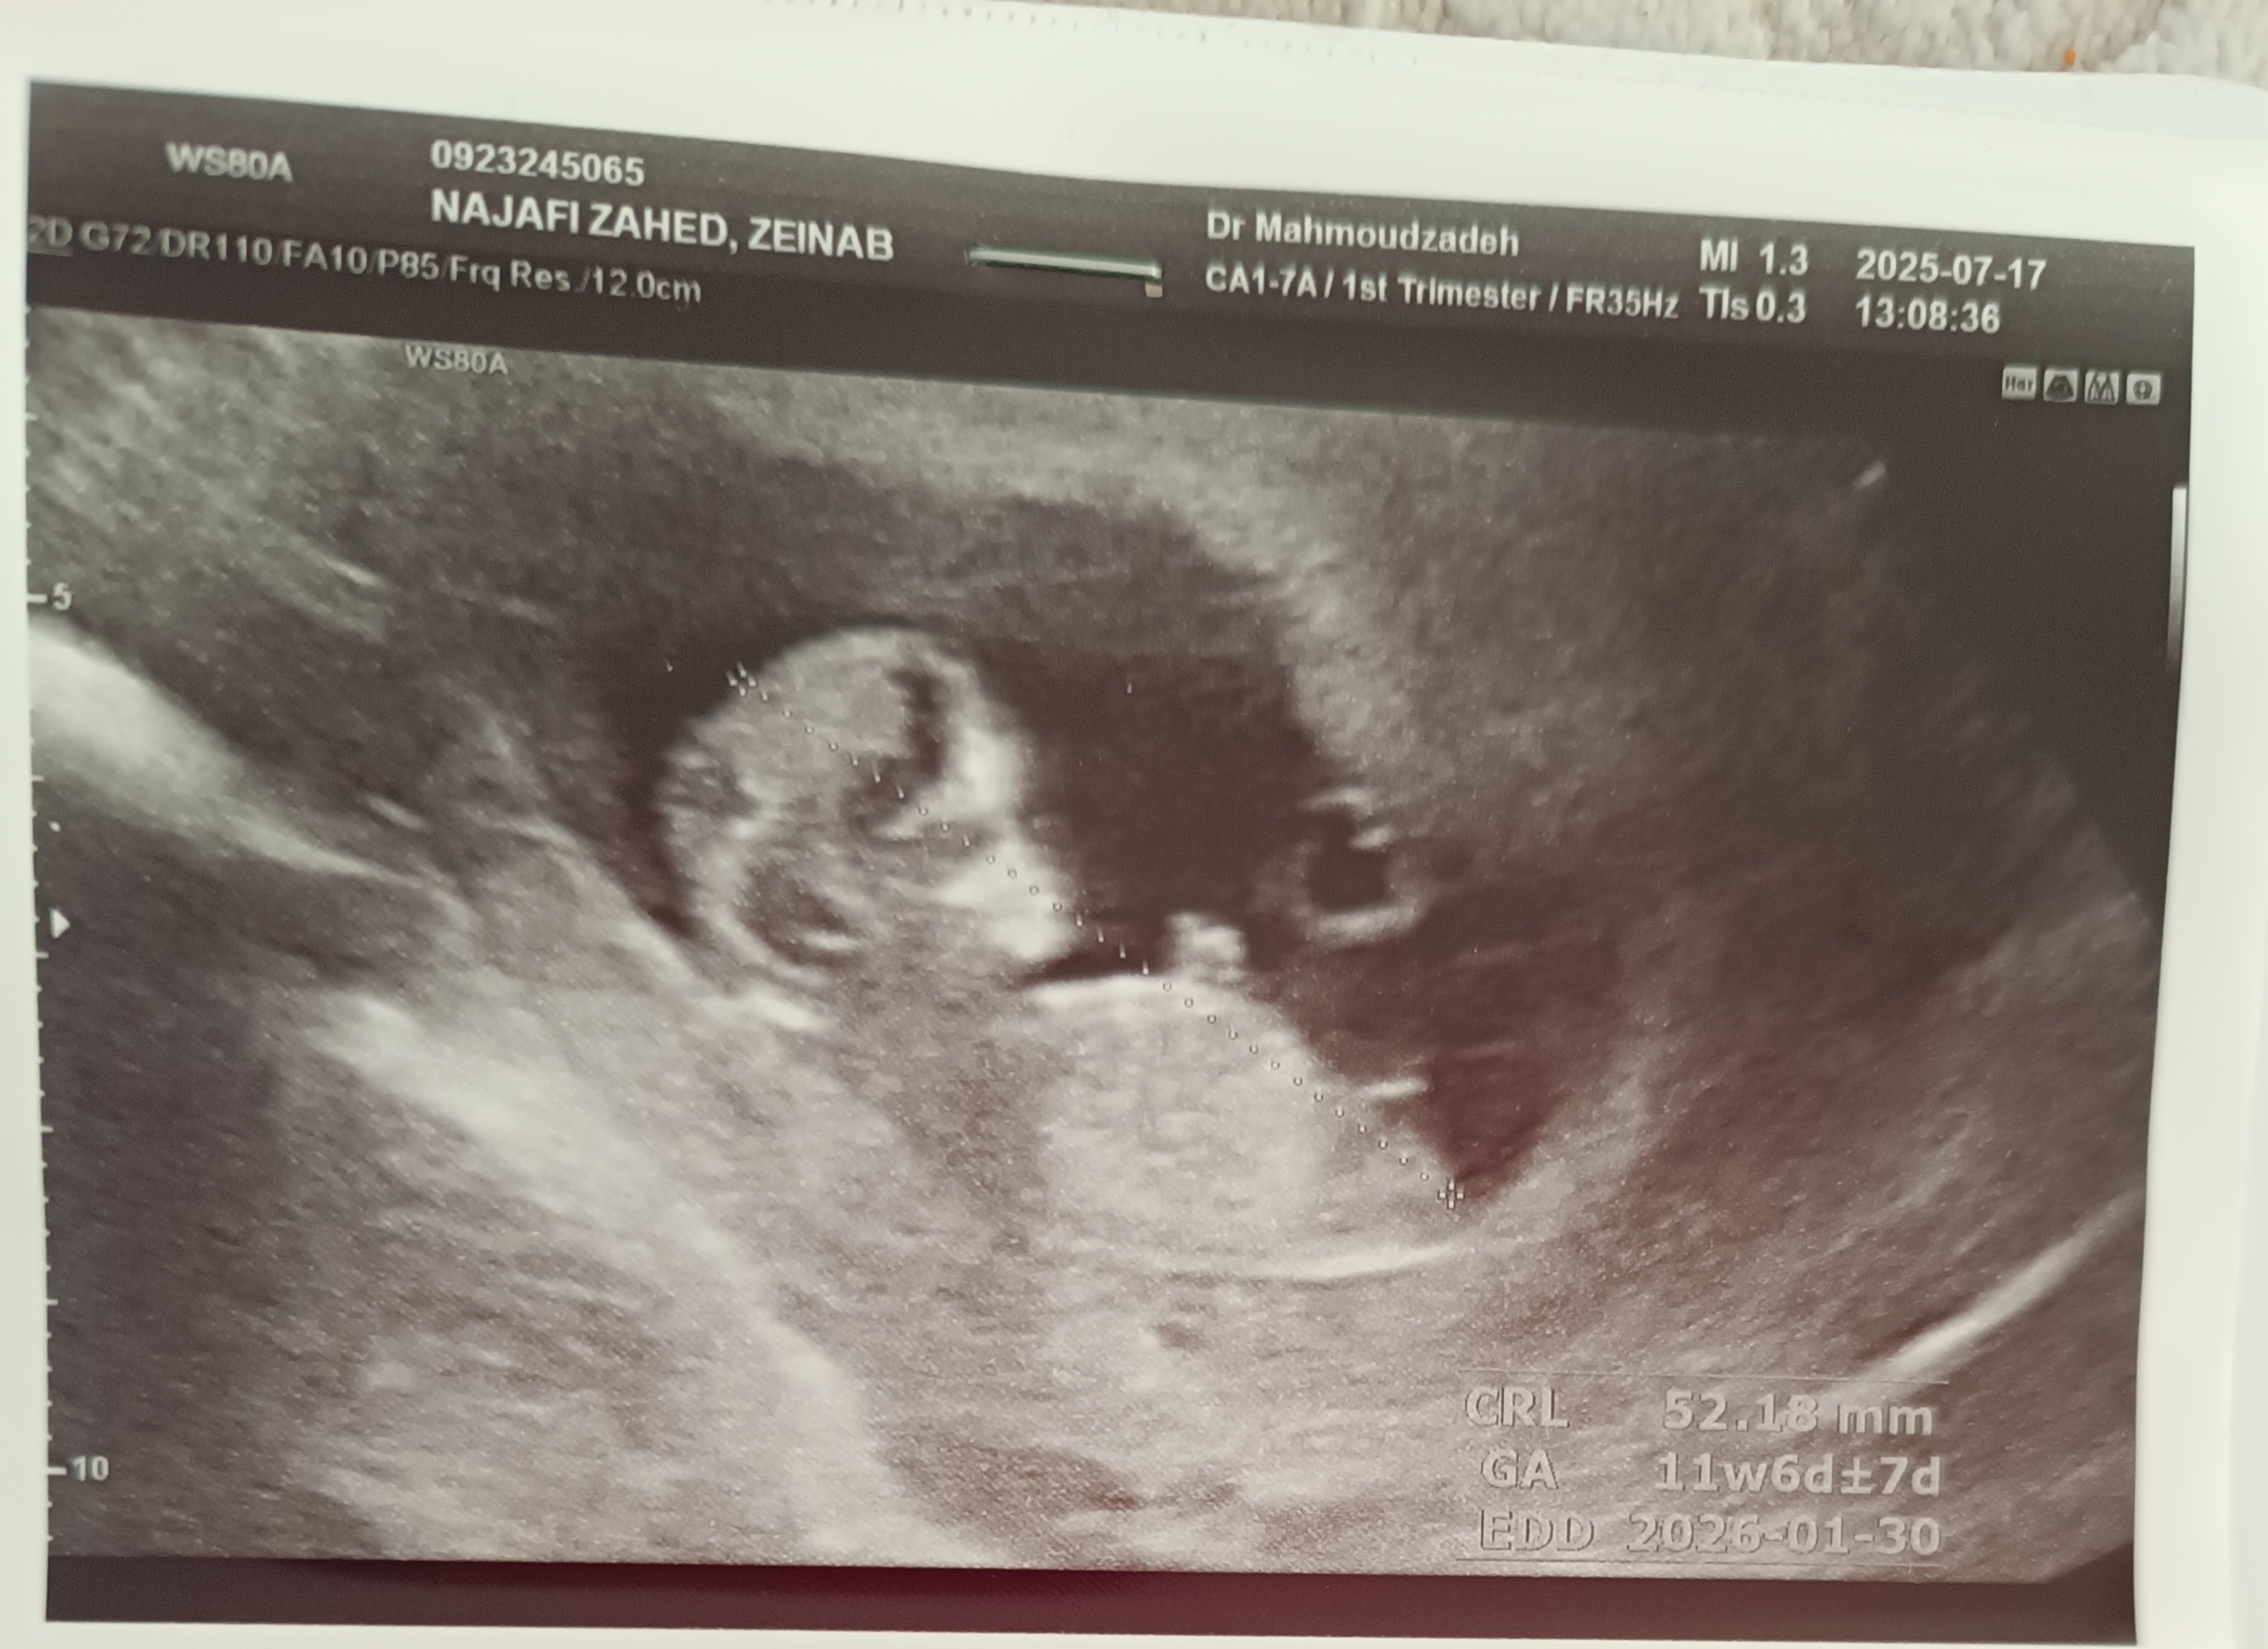

حالت تهوع و  اینا اصلا نداشتم. اشتهام خیلی زیاد شد . علاقه زیاد به تخم مرغ و گوشت و ماهی و... دارم . نفخ و ورم معده دارم و بی خوابی دارم و تمایل به شوری و پاپ کرن پنیری و پفک و این جور طعم ها .